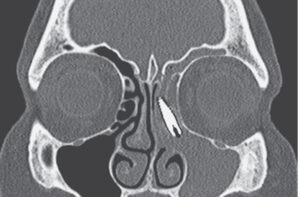

Recentemente, aqui no consultório, vivenciei um caso que ilustra bem essa realidade. Uma paciente chegou com uma história que parecia um pesadelo: o implante dentário que ela havia colocado foi parar dentro do nariz dela, na cavidade nasal! Em vez de uma base sólida para sua prótese protocolo, ela se viu com um problema sério. Agora, terá que passar por um novo tratamento dentário: remover o implante dentário mal posicionado, tratar a área afetada e, só então, reiniciar o processo para instalar corretamente o implante dentário e fixar sua prótese sobre implante. É um caminho mais longo, com custos extras e um peso emocional, como carregar uma mochila pesada em uma trilha que já era desafiadora.

Mas por que esses erros na implantodontia acontecem? Muitas vezes, é como dirigir sem um GPS confiável. Sem um planejamento adequado, usando exames como a tomografia computadorizada (CBCT), o dentista pode perfurar o seio maxilar ou invadir a cavidade nasal. Isso pode levar a infecções, dores e a necessidade de refazer todo o protocolo dental. Procedimentos como o All-on-4 (onde quatro implantes dentários sustentam uma arcada inteira) ou o implante zigomático (fixado nos ossos da bochecha para casos de grande perda óssea) exigem precisão extrema. Um erro de posicionamento pode comprometer toda a estrutura da prótese protocolo, exigindo remoções e novas cirurgias.